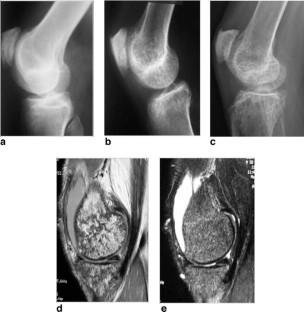

Fibrogenesis imperfecta ossium: MR imaging of the axial and appendicular skeleton and correlation with a unique radiographic appearance

We describe a distinctly unusual MR appearance of the cancellous bone never before described in a patient with biopsy-proven fibrogenesis imperfecta ossium.

Fig. 3